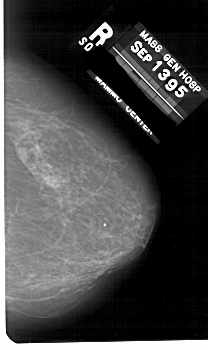

A_1676_1.RIGHT_CC

RIGHT_CC LINES 5236 PIXELS_PER_LINE 3106 BITS_PER_PIXEL 12 RESOLUTION 43.5 NON_OVERLAY